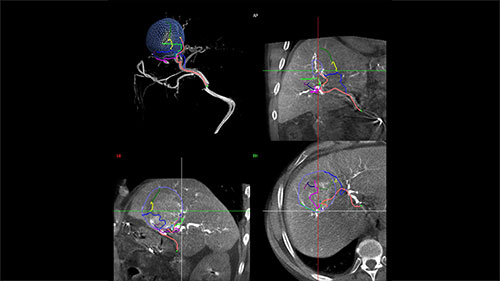

Step 2 – Reach

Based on these images, EmboGuide’s automatic feeder detection can detect significantly more feeding vessels than the current treatment standard of DSA.² ⁴

Live Image Guidance then supports selective or super-selective approaches to the embolization target.

Guidance EmboGuide 1 LM